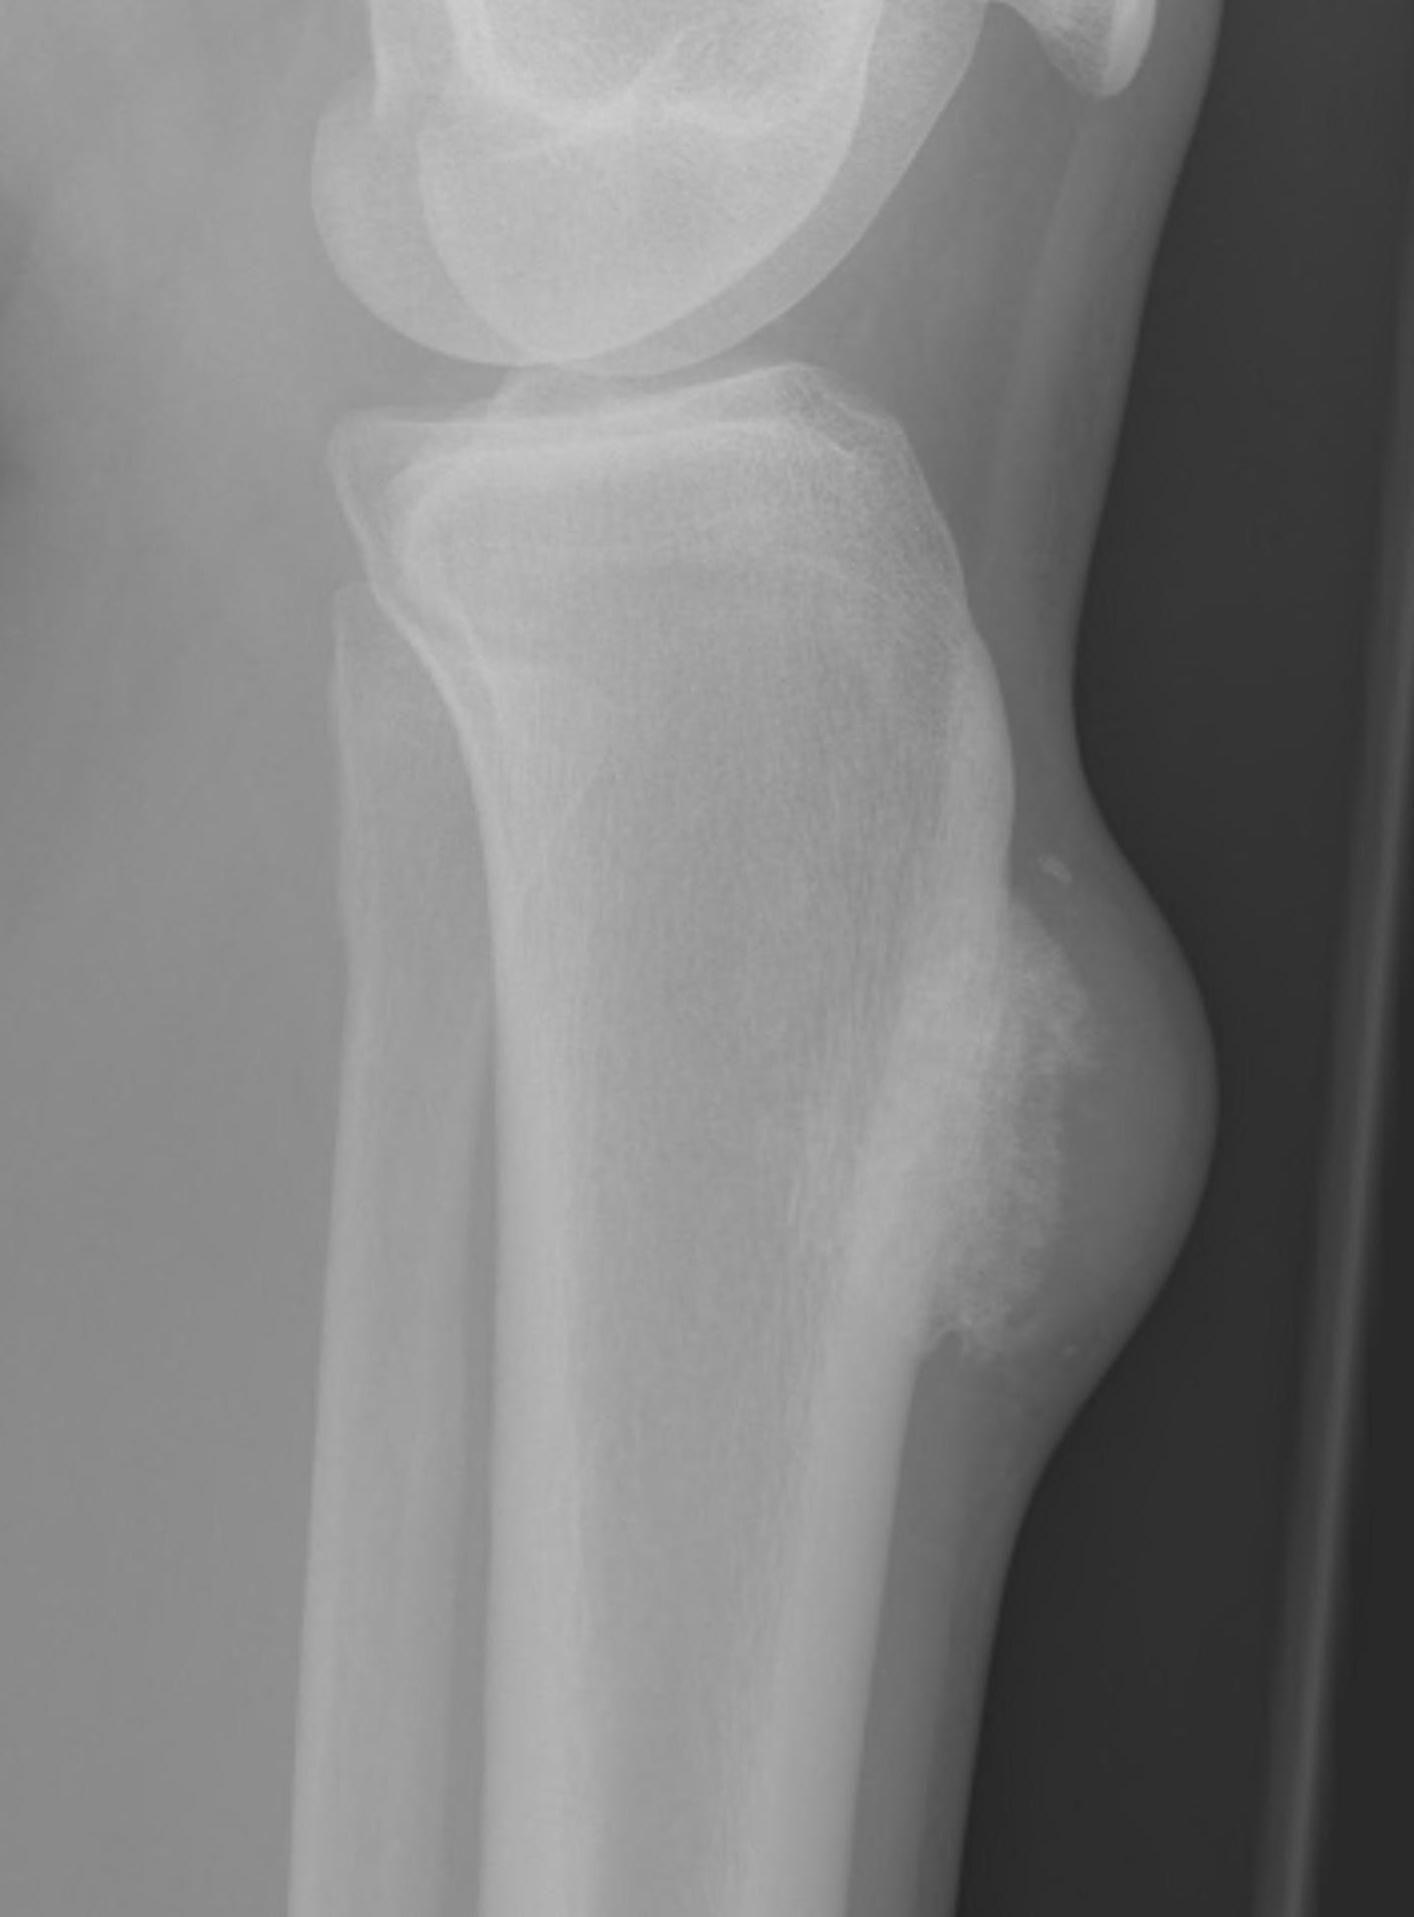

X-ray

May look like osteochondroma

- large lobulated broad-based lesion

- mature bone arising from cortex

- underlying cortex may be thickened

- 25% invade periosteum

"String Sign"

- wraps around bone with intervening periosteum

- well-defined radiolucent line between lesion & cortex

Parosteal Osteosarcoma proximal tibia